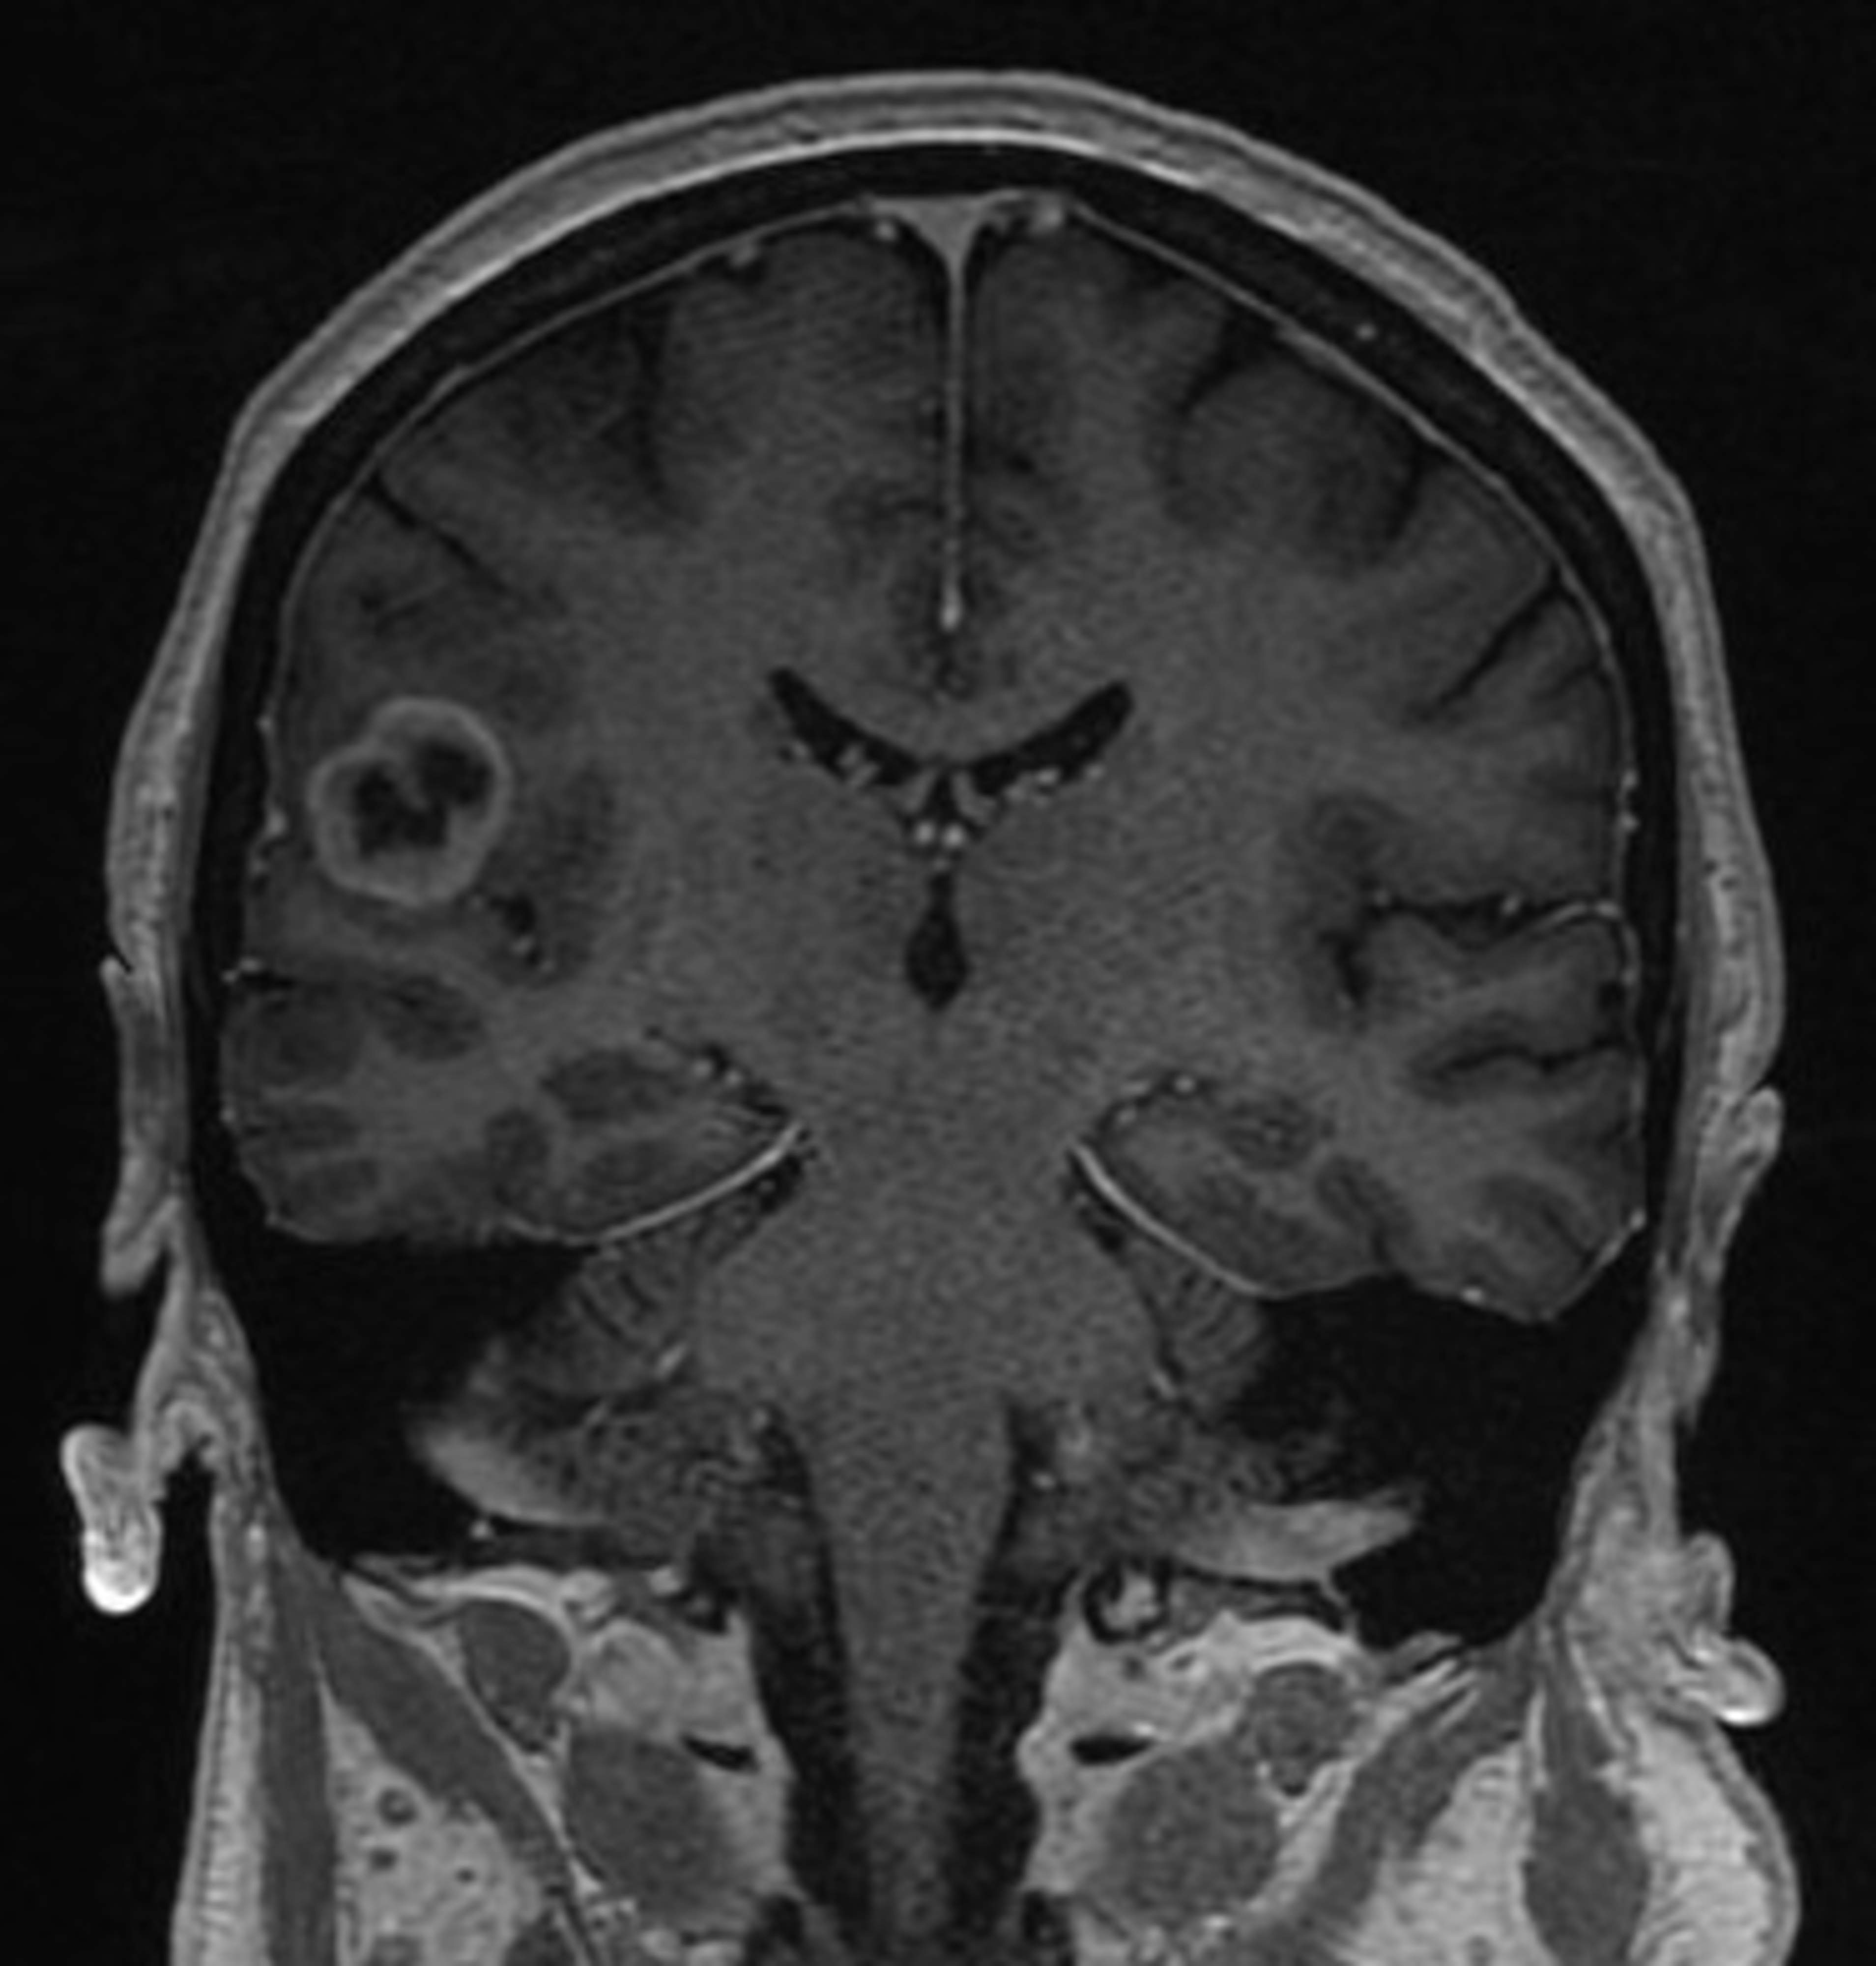

Gliom växer inuti hjärnan bland nervcellerna, med otydlig avgränsning. Utanför det mest täta tumörområdet finns det ofta enstaka tumörceller till och med i den andra hjärnhalvan. Gliom kan uppstå i alla åldrar, men är vanligare hos äldre personer.

Behandlingsformerna för gliom omfattar operation, strålbehandling och cytostatikabehandling. Vid operationen används ett kirurgiskt mikroskop för att avlägsna tumören så exakt som möjligt, men i de flesta fall blir det fortfarande lite kvar av tumören i närheten av operationshålan.